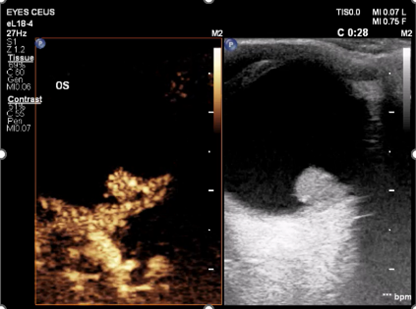

超声检查不仅能够直观的观察眼部病变形态结构,更是目前唯一能够反应眼部血管血流动力学的影像学检查方法。然而由于眼部血管分布密集表浅,普通超声检查的分辨力和敏感性无法满足精准诊断的临床需求。超微血流成像技术是一种新型的可以检测出高分辨率和最小伪影的小血管血流的检测方法,可以用于检测组织中缓慢和微弱的血流解剖。但对于视网膜动静脉栓塞,高血压、糖尿病等视网膜病变,肿瘤病变良恶性鉴别等仍存在不足。近年来随着超声造影技术的迅速发展,超声造影技术对微小血管和低流速、低流量血流信号具有更高的检出率,并且能更优质的显示组织血流的灌注特点。超声造影其独特的显像特点将在眼部占位,眼部血管性病变中取得更大的发展。将超声造影联合超微血流成像技术应用于眼底病变的观察可能为眼科疾病的诊断和鉴别诊断提供一种创新的融合显像检查方法。